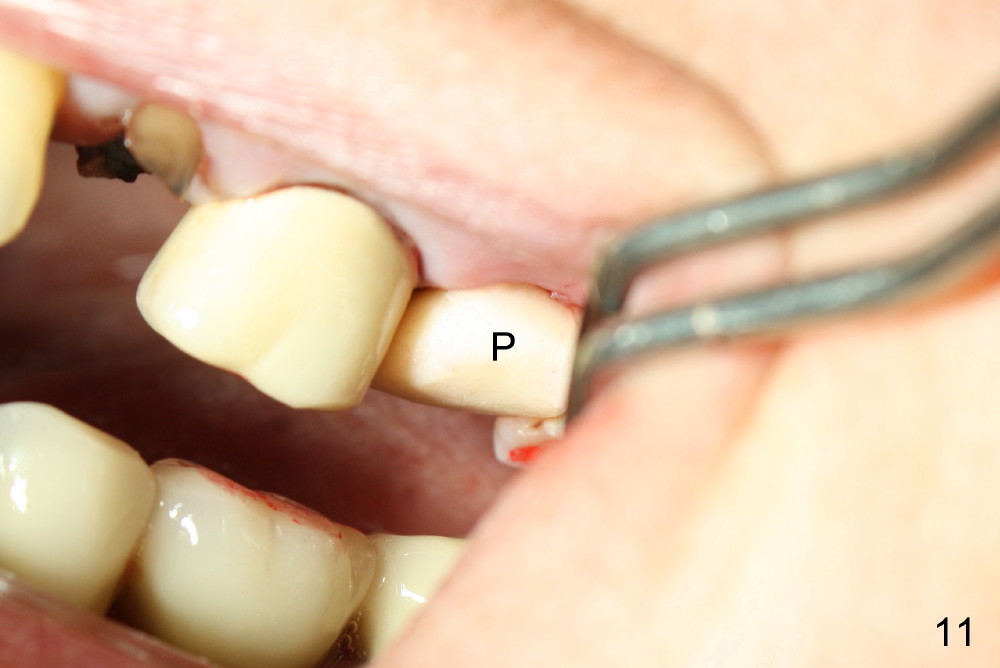

A 66-year-old lady requests restoring a broken tooth (Fig.1). Osteotomy is initiated in a thin septum (Fig.2 (occlusal mirror view) S) by sectioning, drilling and tapping (Fig.3 T). When 7x17 mm tap is removed, the osteotomy is found to form basically in the middle of socket (Fig.4 O). The apical portion of three sockets (Fig.5: MB, P and DB (not labeled) is packed with mixture of autogenous bone and allograft. When a 7x14 mm implant is placed, there are buccal and lingual gaps (Fig.6 *). The latter are bone grafted again (Fig.8 *) and require a coverage. After placement of a 4x3 mm abutment (Fig.7,8 A), an immediate provisional is fabricated (Fig.9 tissue surface view) to cover the remaining sockets (Fig.10 (occlusal mirror view), 11 (buccal view)). The provisional is infra-occlusal, i.e., load-free (Fig.11). The buccal and lingual aspects of the socket are covered by fresh epithelium 8 days postop (Fig.12 <). The implant appears to have osteointegrated 4 months postop (Fig.13). The tooth #16 appears to have shifted mesially. It is difficult to prepare for #15 crown. Luckily the patient agrees to have it extracted because of persistent sensitivity after MO composite. The definitive crown at the site of #15 is cemented 6 months postop (Fig.14).